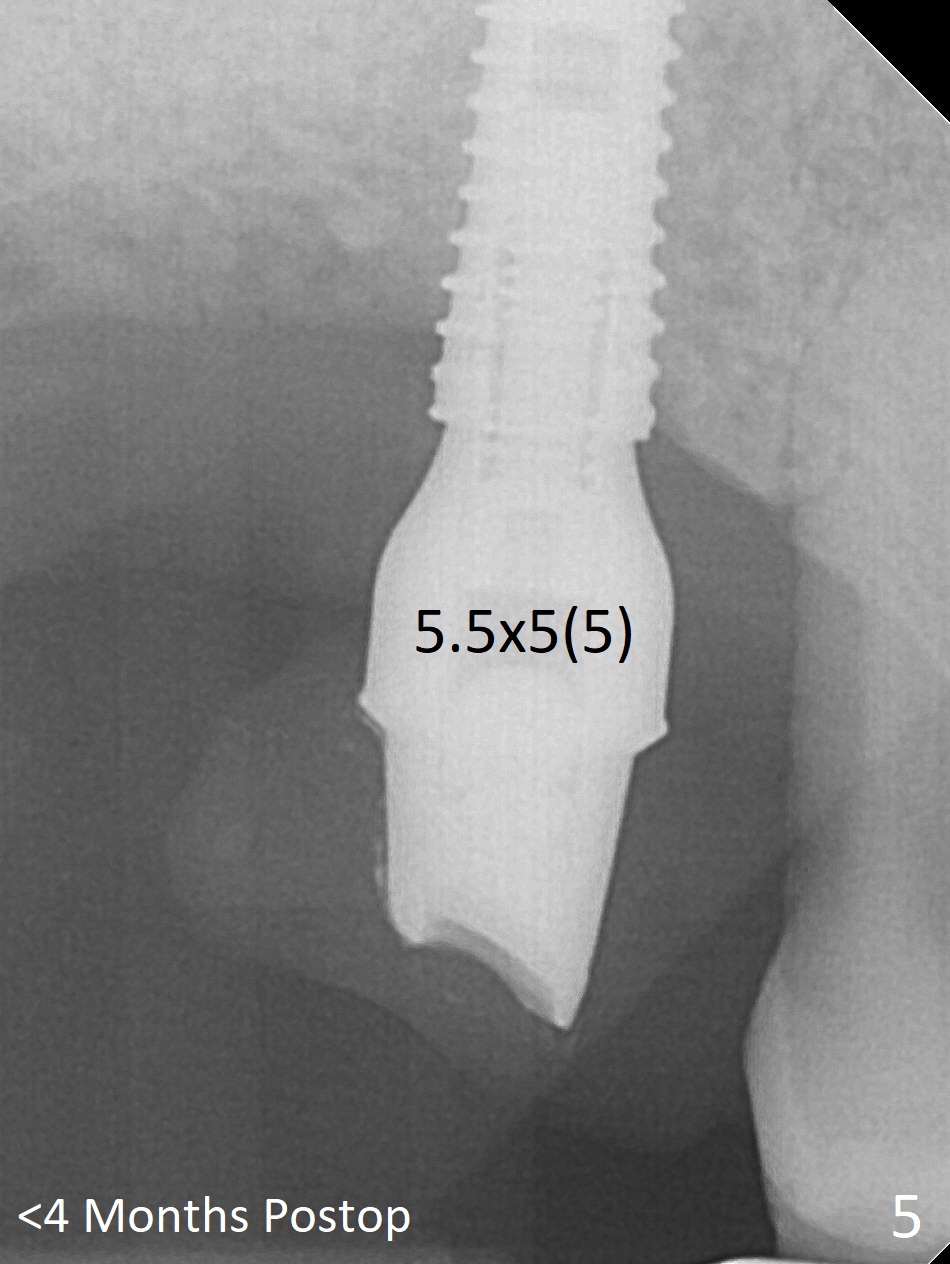

Since the ridge crest at #3 is narrow, Tatum bone scalpels are used to get access and initiate bone expansion, followed by bone blades and RT 2.  It seems that the osteotomy starts mesially; bone height being increased (Fig.1).  When the apical end of the osteotomy tilts mesially, more bone height is obtained.  Drills are alternatively applied because of the hard bone (Fig.2).  A 4x13 mm UF implant is placed initially with the distal threads unburied (Fig.3, >50 Ncm).  With further seating of the implant, a 5.5x5(4) mm abutment is used (Fig.4), which closes the access.  No suture is warranted.  An immediate provisional is fabricated for the patient's comfort and psychological effect.  In fact, the abutment cuff changes to 5 mm prior to temporarization.  There appears no bone loss <4 months postop (Fig.5).  Pulpitis develops at #4 due to DO caries 1 year 5 months post cementation (Fig.6 *).  The crown at #3 is removed for easy and conservative distal carious removal and Cavit temporary restoration to prevent sodium hypochlorite leakage.  Then occlusal access is made for pulpotomy.  When RCT finishes, no crown will be made, but occlusal reduction is required.    The patient returns for RCT 1 month later (Fig.7,8). Cavit remains in place (Fig.7 C).  Although 2 threads are exposed distal (Fig.8 arrow), there is no sign or symptom of periimplantitis, which may be related to the thick gingiva (arrowhead).  Return to Upper Molar Immediate Implant, IBS, #14 (Tissue Punch) Xin Wei, DDS, PhD, MS 1st edition 08/25/2017, last revision 09/08/2019